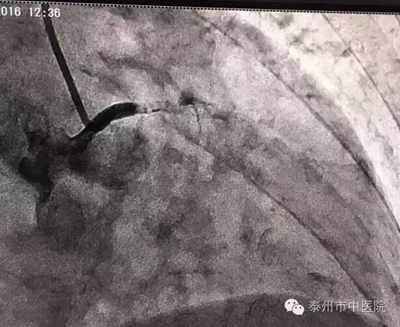

在與家屬溝通后,市中醫(yī)院心血管病科張永光主任等立即至導(dǎo)管室緊急冠脈造影。冠脈造影血管投影只見左主干近端,下方血管無顯影,明確為左主干閉塞。令現(xiàn)場所有醫(yī)護(hù)人員心驚不已!

左主干閉塞,是一例病情兇險、病死率極高的病例!搶救刻不容緩?。堄拦庵魅蔚?,隨即開展緊急救援,長達(dá)一個小時的救治中,左主干再通,X線下可看見清晰的血管顯影。